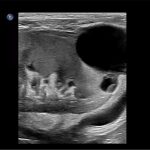

Imagini clinice:

Aplicatii: